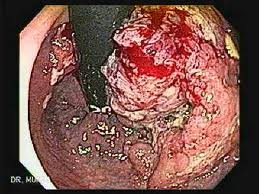

Cáncer de recto

Imagen:

Información: El cáncer del recto es una enfermedad en la cual se encuentra células cancerosas (malignas) en los tejidos del recto. El recto forma parte del aparato digestivo. El aparato digestivo extrae y procesa los nutrientes (como las vitaminas, los minerales, los carbohidratos, las grasas, las proteínas y el agua) de los alimentos y guarda los desechos hasta que sean expulsados del cuerpo. El aparato digestivo está formado por el esófago, el estómago y los intestinos delgado y grueso. Los últimos 6 pies de intestino se denominan intestino grueso o colon, mientras que las últimas 6 pulgadas constituyen el recto y el conducto anal. El conducto anal termina en el ano (abertura del recto a la parte exterior del cuerpo).

El cáncer colorrectal, también llamado cáncer de colon, incluye cualquier tipo de neoplasias del colon, recto y apéndice. Se piensa que muchos de los casos de cáncer colorrectal nacen de un pólipo adenomatoso en el colon. Estos crecimientos celulares en forma de hongo son usualmente benignos, pero de vez en cuando se vuelven cancerosos con el tiempo. En la mayoría de los casos, el diagnóstico del cáncer localizado es por colonoscopia. El tratamiento es por lo general quirúrgico, y en muchos casos es seguido por quimioterapia.

La patología del tumor de colon se reporta por lo general del análisis de tejido obtenido de una biopsia o una operación. El reporte patológico usualmente contiene una descripción del tipo de célula y el grado de avance. El tipo más común de célula cancerígena es el adenocarcinoma, el cual ocupa un 95% de los casos. Otros tipos menos frecuentes incluyen los linfomas y el carcinoma de célula escamosa.

El cáncer del lado derecho (colon ascendente y ciego), tiende a tener un patrón exofítico, es decir, el tumor crece hacia la luz intestinal comenzando desde la pared de la mucosa. Este tipo raramente causa obstrucción del paso de las heces y presenta síntomas como anemia. El cáncer del lado izquierdo tiende a ser circunferencial, y puede obstruir el intestino al rodear la luz del colon.